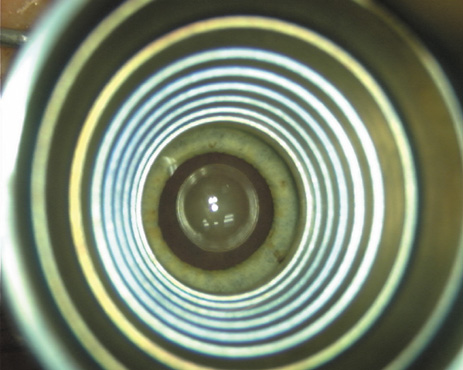

Proper centration of the incisions over the steep corneal meridian is of utmost importance. Increasing evidence supports the notion that significant cyclotorsion may occur when assuming a supine position.32 As previously noted, an axis deviation of only 15 degrees may result in a 50% reduction of surgical effect.5 For this reason, most surgeons advocate placing an orientation mark at the 12:00 or 6:00 limbus while the patient is in an upright position. This is particularly important when employing injection anesthesia wherein unpredictable ocular rotation may occur. An additional measure that may be employed to help center the relaxing incisions is to identify the steep meridian (plus cylinder axis) intraoperatively using some form of keratoscopy. The steep meridian over which the incisions are to be placed corresponds to the shorter axis of the reflected corneal mire. A simple handheld device such as the Maloney (Storz, Katena) or Nichamin (Mastel Precision) keratoscope works well, or a more robust and well-defined mire may be obtained through an elaborate microscope-mounted instrument such as the Mastel Ring of Light (Mastel Precision). Another common way in which the steep meridian is marked utilizes a Mendez Ring or similar degree gauge that is aligned with the previously placed limbal orientation mark, and the cylinder axis is then located on the 360-degree gauge.

The extent of arc to be incised may be demarcated in several different ways. Our preferred method makes use of a modified Fine-Thornton fixation ring (Nichamin Fixation Ring and Gauge; Mastel Precision, Storz, Rhein Medical). This instrument serves to fixate and position the globe in order to optimize incision placement, as well as to delineate the extent of arc to be incised. One visually extrapolates from the limbus to marks on the surface of the ring. Each incremental mark is 10 degrees apart, and bold hash marks (180 degrees) opposite to each other serve to align and center the incision over the steep meridian. This approach obviates the need to ink and physically mark the cornea. If one desires, particularly when first gaining experience with LRIs, a two-cut RK marker may be used to place ink marks upon the cornea to show the exact extent of arc that is to be incised, in conjunction with the fixation ring/gauge (Fig. 4). Alternatively, various press-on markers are available, such as those made by Rhein Medical (Dell-Nichamin Marker, Nichamin-Kershner Marker, or the Ruminson Marker) (Fig. 5). ASICO and other instrument companies offer a full line of dedicated markers, rings, and blades for performing LRIs.

Fig. 8. Steep meridian is confirmed intraoperatively by keratoscopy. In this left eye viewed from the temporal side, the “short axis” of the corneal mire is seen to be at the 75-degree meridian. (Reprinted from Hardten DR, Lindstrom RL, Davis EA. Phakic Intraocular Lenses: Principles and Practice. Thorofare, NJ: SLACK Incorporated, 2004, with permission.)